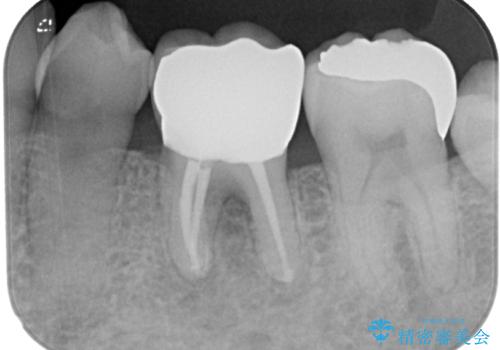

根管治療を行った奥歯は、再発防止や残された歯質を守るため、クラウンによる補綴治療が必要となります。

補綴後6ヶ月経過しレントゲンを撮影したところ、根尖周辺の病変が消失していることが確認できました。